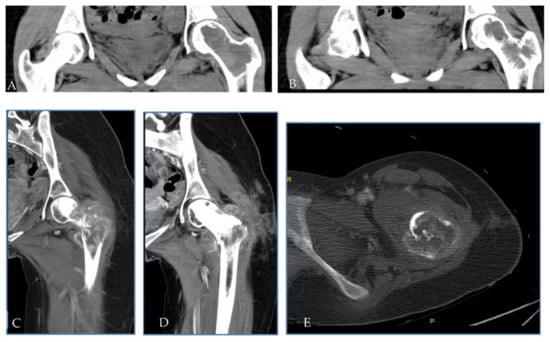

2.2. Patient 2

| Pt 2 | 48 | M | 0 | 16 November | Right tibia | Curettage and bone grafts | 20 October | Neoadj denosumab (6 cycles) | 21 February Extraarticular resection: malignant transformation of GCTB | EURO BOSS | NED | - | FU 21 December | 51 | 64 | 13 |